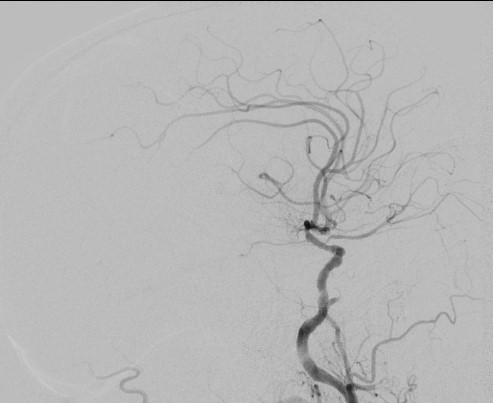

13:00 Больной подан в рентгеноперационную, выполнена церебральная ангиография: Ангиографические признаки атеросклеротического процесса брахиоцефальных артерий, тромботической окклюзии правой ВСА(Рис1), окклюзия левых ВСА(Рис3) и ПА(Рис2).

рис. 1 рис. 2

рис. 3 рис. 4